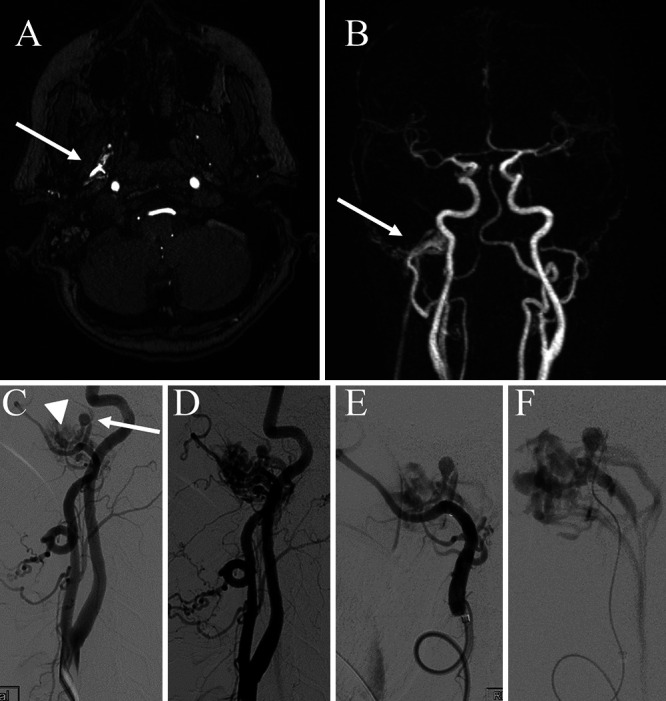

The patient reported symptoms of pulsatile tinnitus 2 weeks after the procedure and demonstrated a right preauricular bruit on a physical exam. Magnetic resonance angiography of the head demonstrated an extracranial fistulous connection of unclear etiology (Fig. 2A and B). Digital subtraction angiography was subsequently performed, which demonstrated an MMA to pterygoid plexus fistula as well as an MMA pseudoaneurysm (Fig. 2C–F).

FIG. 2.

A: Axial magnetic resonance imaging (MRI) demonstrating an extracranial fistulous connection in the infratemporal fossa resulting in early filling of the pterygoid plexus (arrow). B: Reconstructed coronal maximal intensity projection (MIP) images demonstrate an extracranial carotid connection to the plexus with early filling of the venous network in the arterial phase (arrow). C: Lateral common carotid artery injection demonstrating early venous filling of the pterygoid plexus (arrowhead) and pseudoaneurysm formation arising from the MMA (arrow). D: Slightly more delayed arterial injection with more prominent venous filling. E and F: More selective injection along the internal maxillary artery and super selective injection of the pseudoaneurysm, respectively.